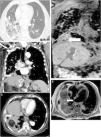

A: Axial cut computerized tomography. Pulmonary infiltrates patched with airborne bronchogram (thick arrow) and areas of tarnished glass predominantly right lower lobe (arrowhead).

Figure 1B: Coronal cut computerized tomography. A small abscess is shown in the diaphragmatic region (thick arrow) and calcified hydatid cyst (arrowhead).

Figure 1C: Axial cut computerized tomography. Abscess (thick arrow) between the posterior hepatic rim and the lower right lobe, with a small air bubble inside.

Figure 1D: Coronal cut of hepatic magnetic resonance imaging in hepato-specific phase with bile duct contrast excretion at the same level as Figure 1B. Abscess (thick arrow) and fistulous path (thin arrow) are shown.

Figure 1E: Axial cut of hepatic magnetic resonance imaging in hepato-specific phase with bile duct contrast excretion at the same level as Figure 1C. Fistulous tract (thin arrow) and abscess (thick arrow) leading to the anterobasal segment of the lower right lobe.